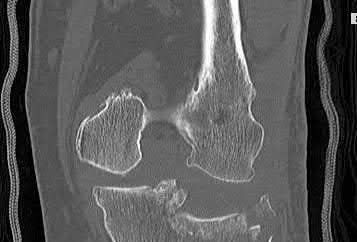

Figures A and B are the Lateral and AP radiographs of a displaced talar neck fracture with tibiotalar dislocation. Figures C and D are the post-reduction sagittal foot CT cuts that reveal a displaced talar neck fracture with medial

comminution.